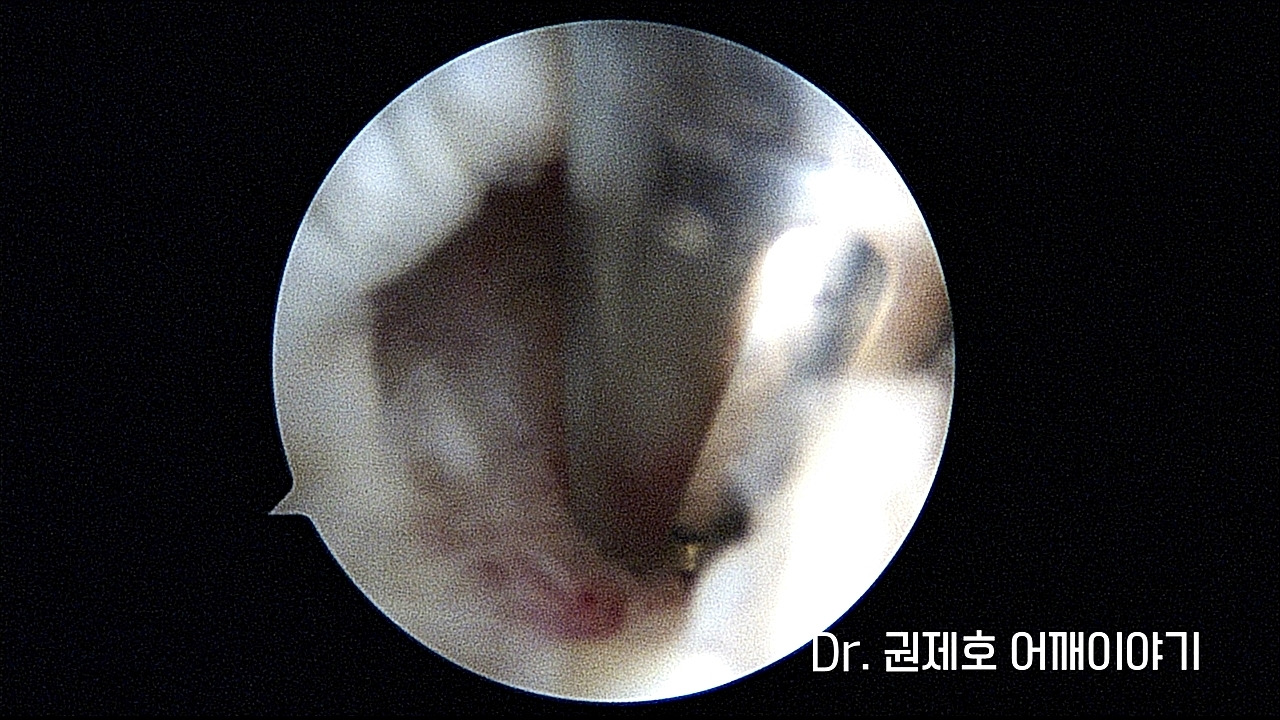

끊어진 회전근개를 다시 붙이기 위해 인대가 붙을 부위에 전처리를 시행합니다.

그러고 나서 앵커라고 하는 실들이 달린 기구를 이용하여 뼈에 삽입을 시켜 고정시킵니다.